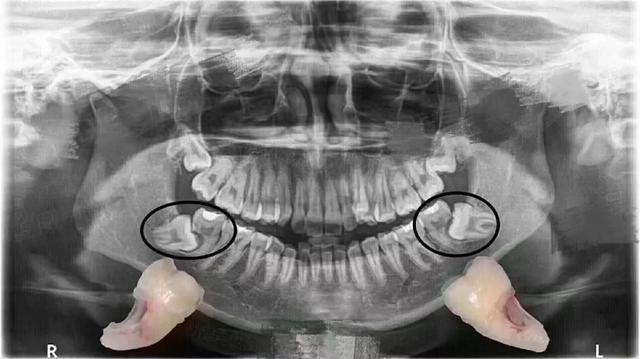

智齿水平生长,不痛,前面的牙齿被顶坏,结果就是两个都拔掉 - 好大夫

智齿把临牙顶坏了.

智齿前倾阻生,近中牙冠邻合面深龋.